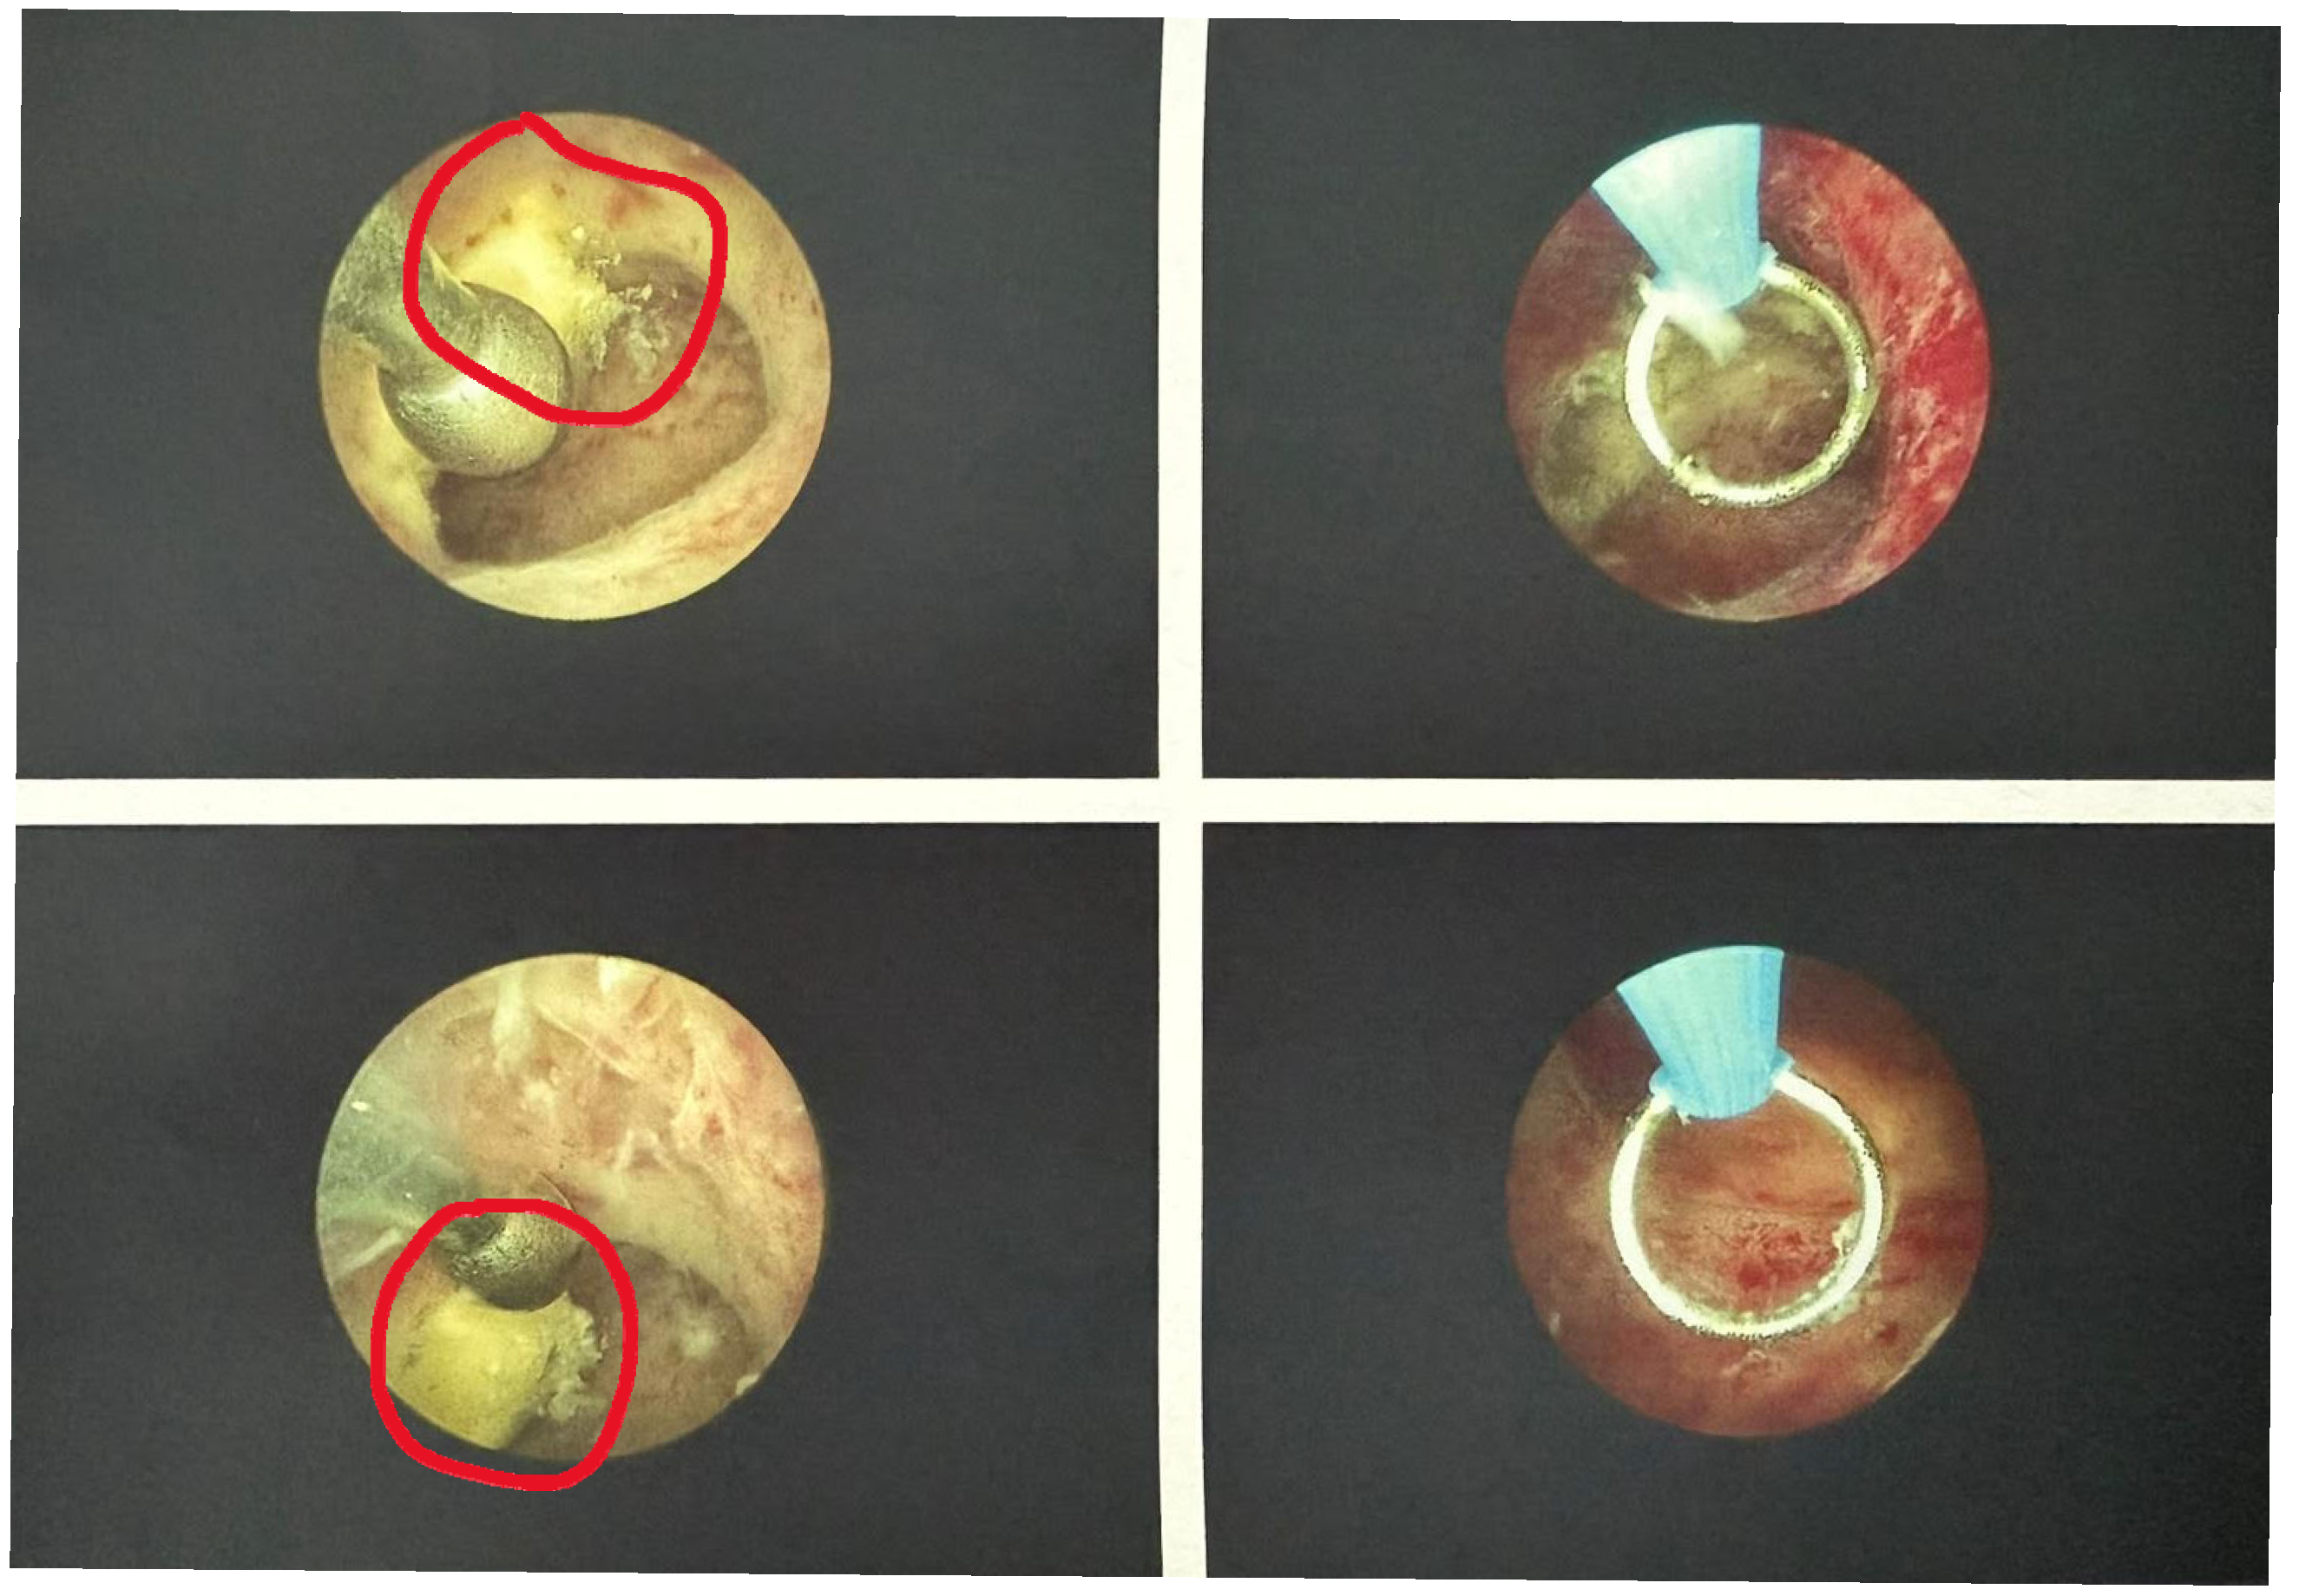

Upon entry into the uterine cavity, a 1.5 cm whitish, avascular residual amniochorionic fragment was identified on the right lateral wall. The surrounding endometrium appeared homogeneous, with no evidence of atypical vascularization, placental bed disruption, or signs suggestive of gestational trophoblastic disease.

The pathological tissue was resected using a single-use bipolar cutting loop, performing smooth shaving movements under continuous visualization. The bipolar technology ensured precise excision with minimal thermal spread. Tissue removal proceeded without bleeding or need for coagulation. Visibility remained optimal throughout the procedure with stable uterine distension.

The total operative time was 7 min, from insertion of the hysteroscope to removal. No intraoperative complications occurred, and no additional instrumentation was required (Figure 2).

Figure 2. Hysteroscopic view before (left) and after (right) resection of the amniochorionic tissue.